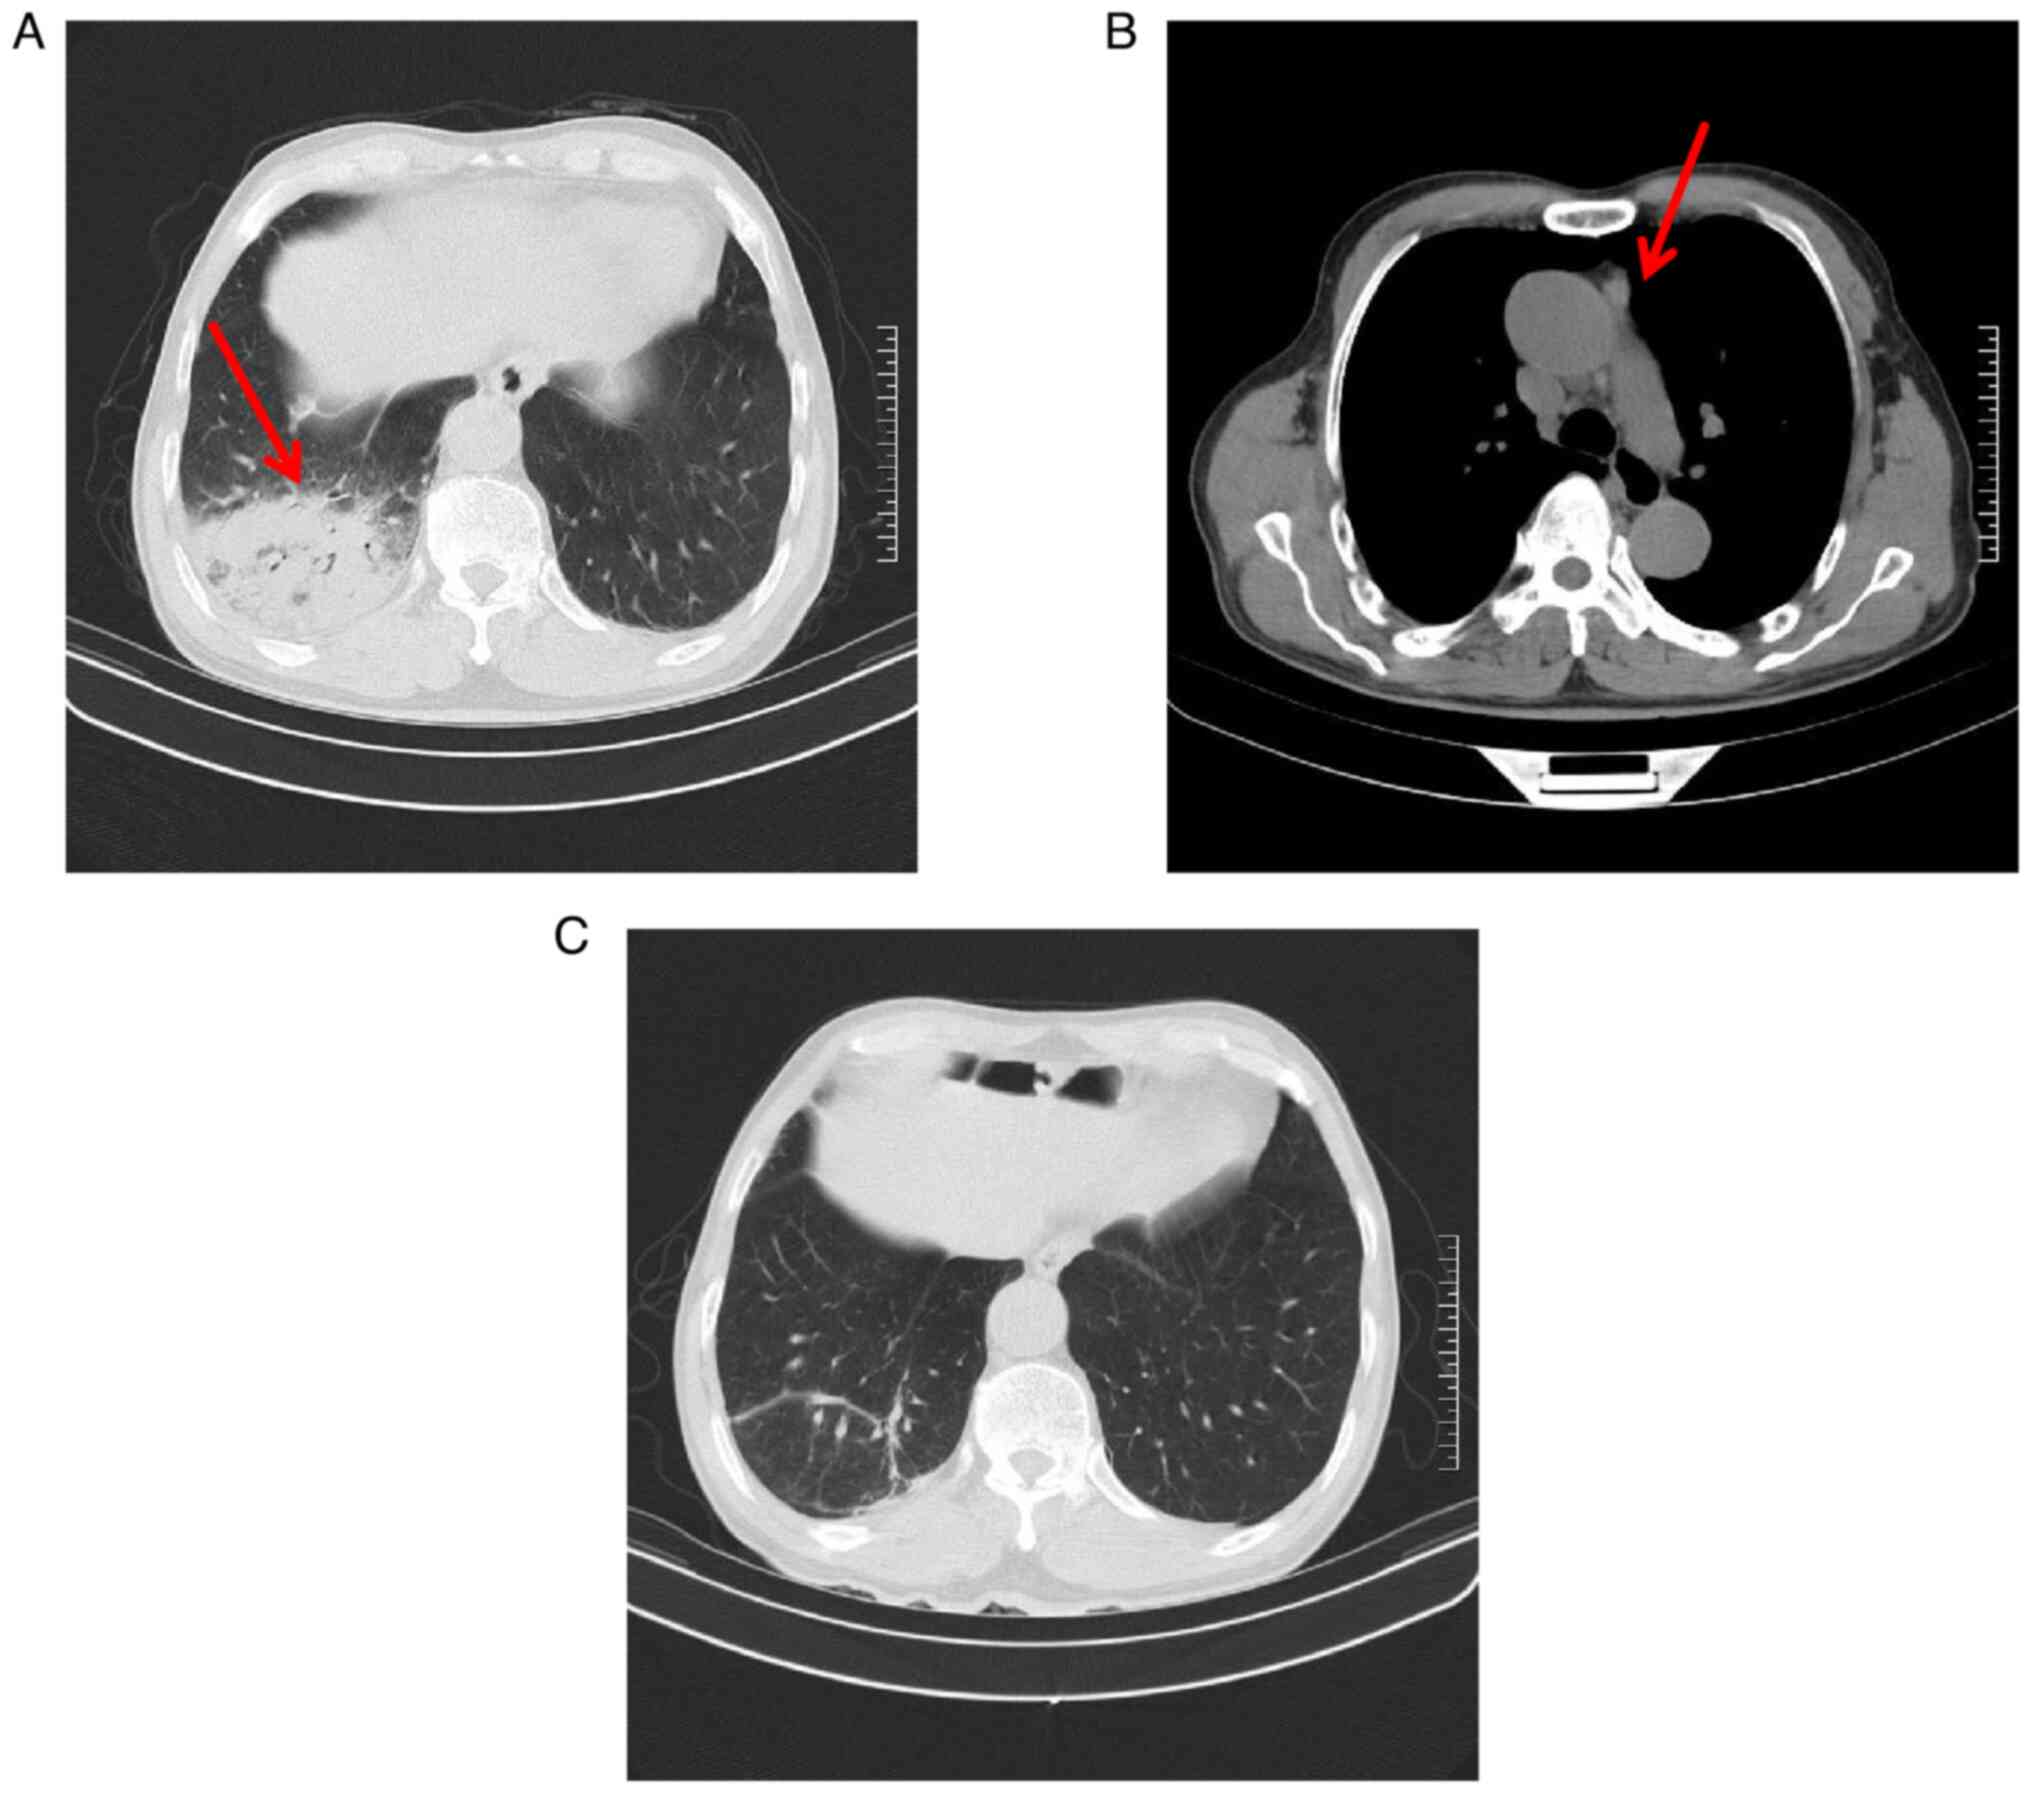

The case of a patient with type B3 thymomacomorbid with Chlamydia psittaci (C. psittaci) pneumonia exhibiting rare features is presented in the current report. The patient was admitted at the Second Affiliated Hospital of Jiaxing University (Jiaxing, China) with a history of direct contact with poultry. Clinical manifestations included fever, shivers, cough, fatigue and poor appetite. Chest computed tomography (CT) indicated right lung pneumonia, while metagenomics next‑generation sequencing using bronchoalveolar lavage fluid confirmed infection with C. psittaci. Additionally, positron emission tomography‑CT suggested the presence of thymoma. After surgery and treatment with doxycycline and imipenem cilastatin, the patient was discharged showing signs of improvement.

Figure 1